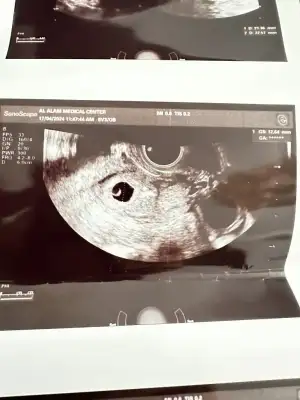

Merhaba.5+2 . Kese var ama bebek gözükmedi. Benim ultrasoni da bakabilir misiniz rica etsem😢

Eklentiler

• IMG_1487.webp

IMG_1487.webp

32,8 KB · Görüntüleme: 270